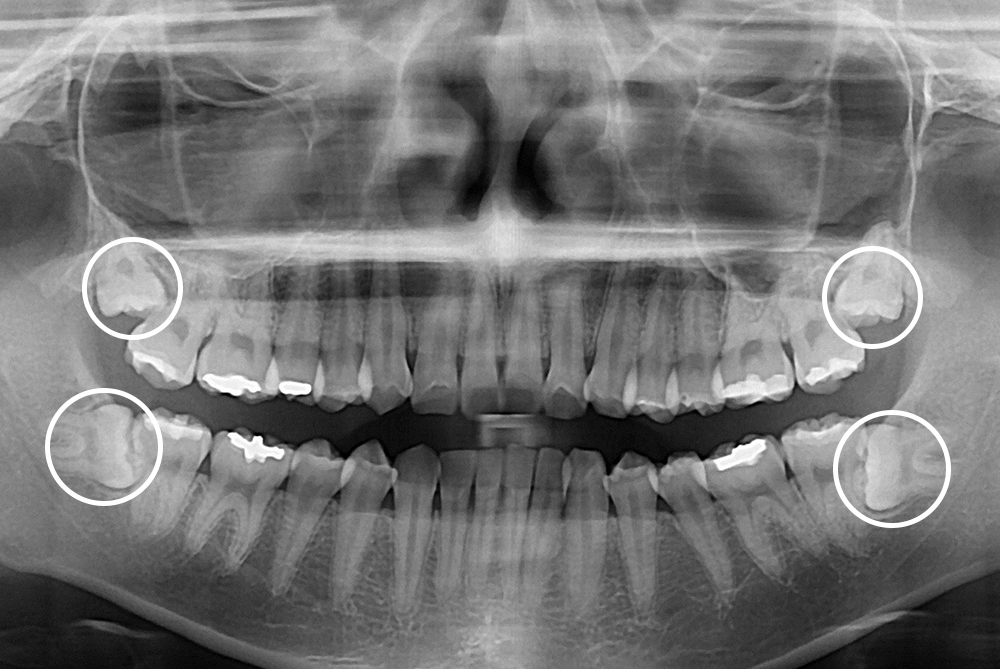

[사랑니] 매복 사랑니 발치

치료전 : 2016-08-05